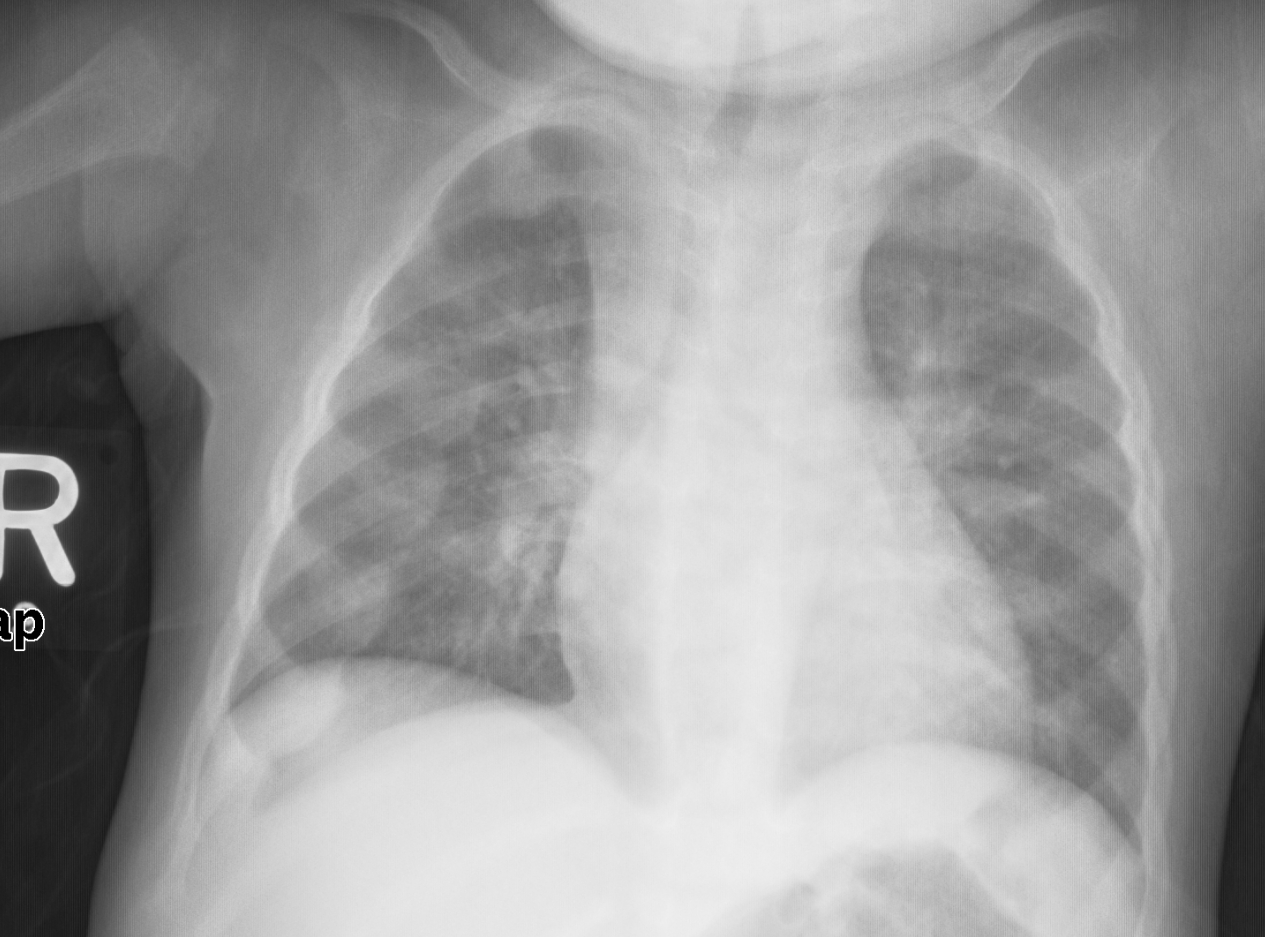

어린아이는 O다리와 두꺼워진 발목과 손목이 있을 수 있으며,[17] 나이가 많은 아이는 안짱다리가 있을 수 있다.[14] 척추 측만증 또는 요추 척추전만증의 척추 만곡이 나타날 수 있다. 골반뼈가 변형될 수 있다. 구루병 염주는 늑골연골관절에 형성되는 결절로 인한 두꺼워짐으로 인해 발생할 수 있다. 이는 몸의 양쪽에 선을 따라 각 늑골의 중앙에 보이는 혹으로 나타나며, 묵주와 비슷하여 그 이름이 붙었다. 비둘기 가슴[14]의 변형으로 해리슨의 홈이 나타날 수 있다.

| 흉부 | 구루병 염주 (늑골의 골연골 결합부의 확대), 깔때기가슴, 새가슴 |